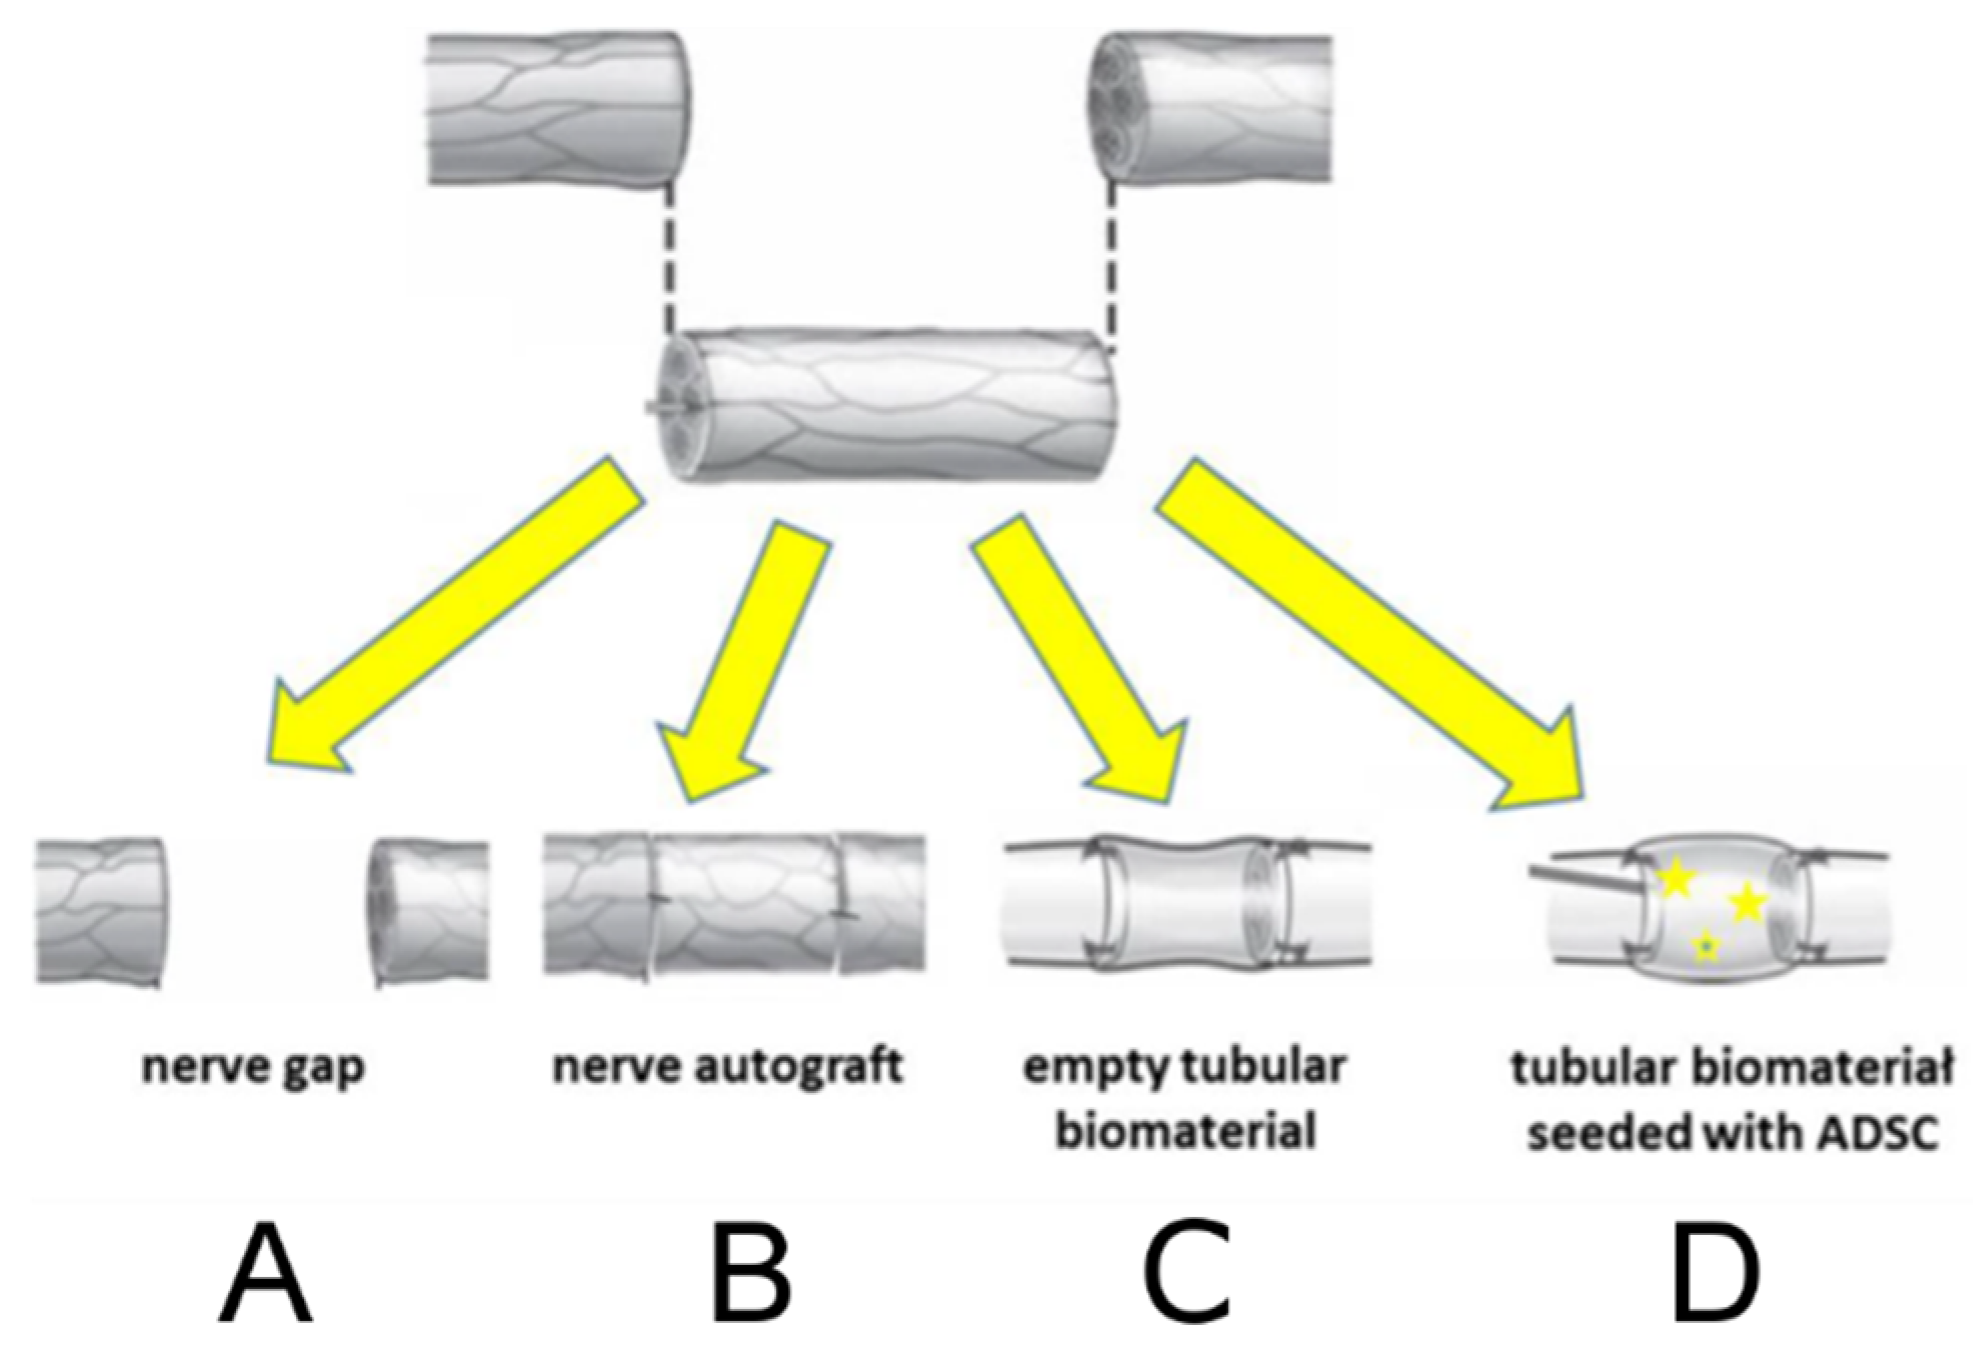

2.3. Animal Study and SFI

| Group | Fibrosis |

|---|---|

| % of Positively Stained Pixels (Mean ± SD) | |

| A | 65.34 ± 12.3 |

| B | 13.61 ± 3.42 |

| C | 15.38 ± 2.81 |

| D | 12.11 ± 2.76 |

| Healthy muscle (n = 7) | 5.11 ± 2.23 |